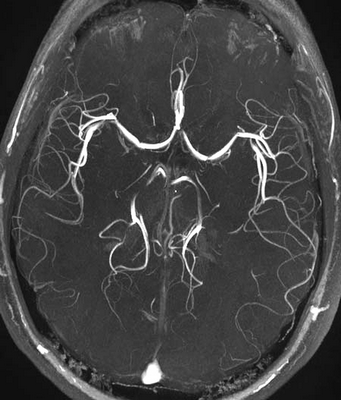

МРТ изображение артерий головного мозга

Магнитно-резонансная томография позволяет не только увидеть строение артерий, но и оценить просвет сосуда и визуализировать сосудистую стенку. Благодаря МРТ диагностика заболеваний стала возможна на самых ранних этапах их возникновения.

МР-изображение артерий мозга

Исследование может проводиться не только для диагностирования заболевания, но и для определения эффективности лечения различных патологий.